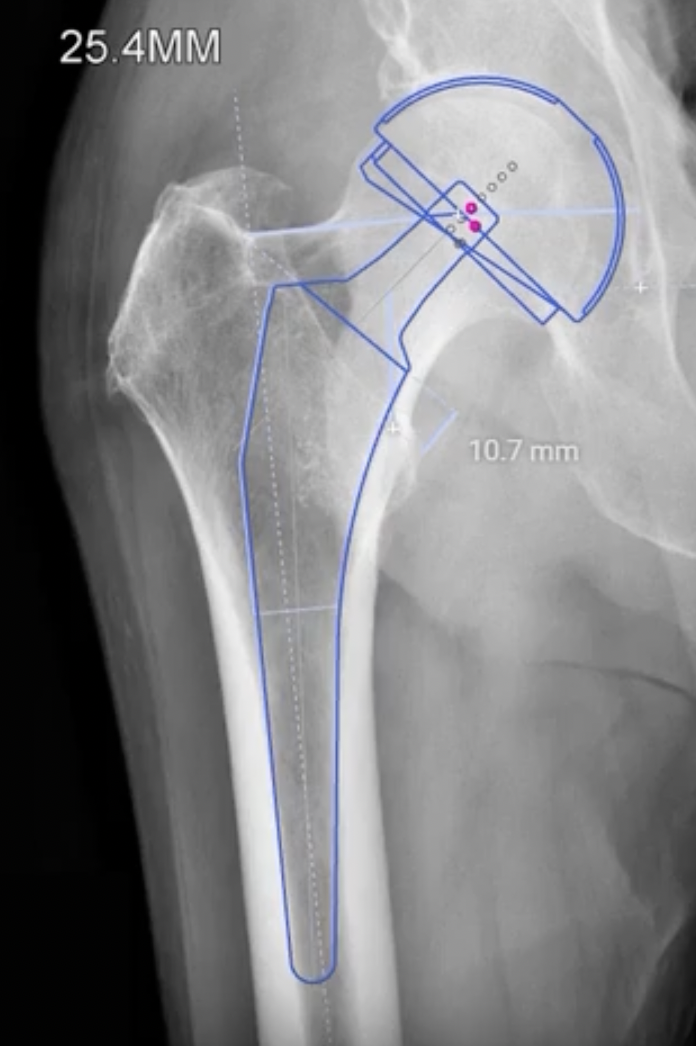

CT templating

Advantage

- extremely precise especially with femoral anteversion / cup inclination and anteversion

- evaluates bone stock

- identify osteophytes